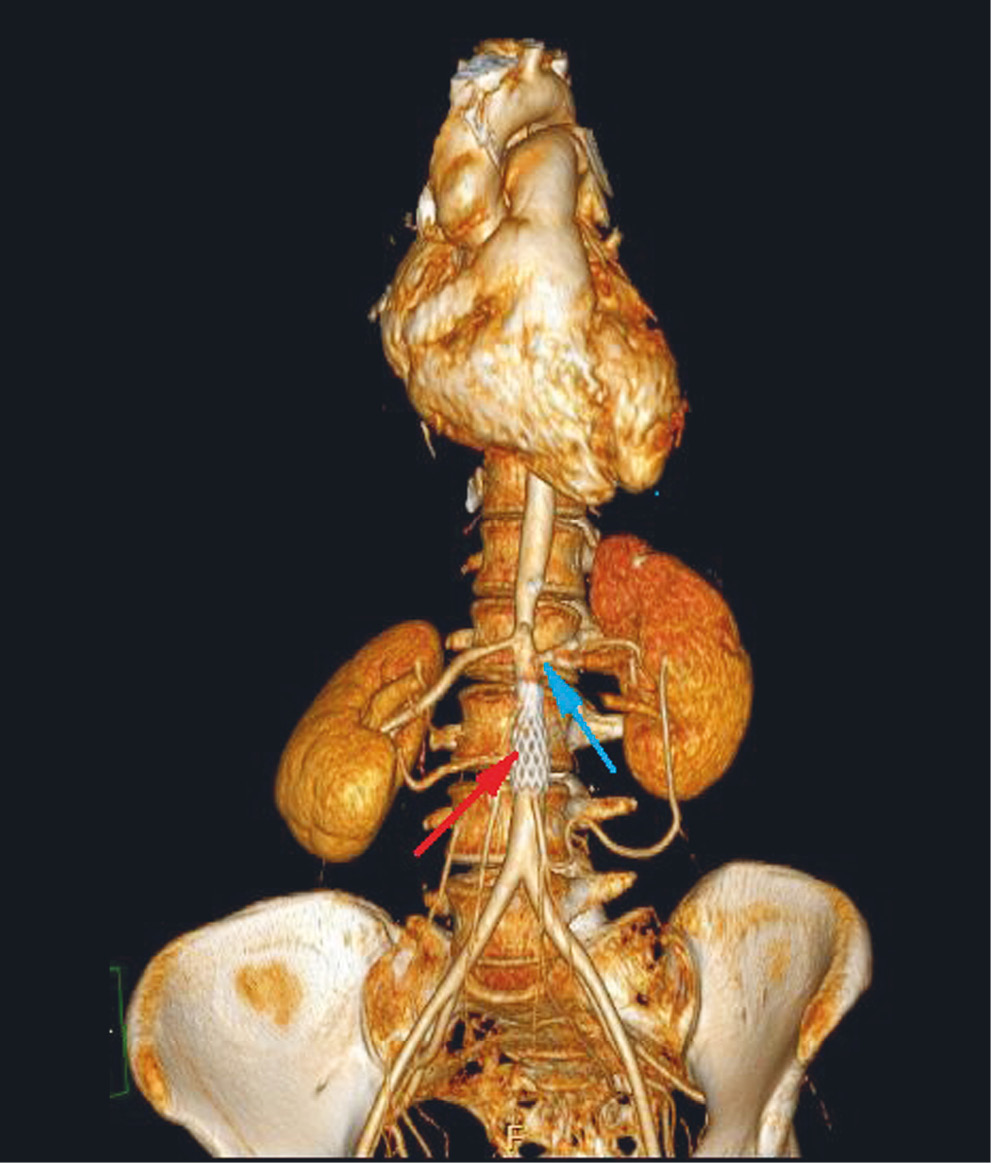

В октябре 2010 г. выполнена мультиспиральная компьютерная томография грудного и брюшного отделов аорты, а также подвздошных артерий, по результатам которой от Th11 грудного до L3 поясничного позвонков выявлено неравномерное циркулярное утолщение стенки аорты (0,4–0,6 см) с неравномерным сужением просвета от 0,7 до 1,1 см; на уровне L3 позвонка отмечалось резкое сужение просвета аорты до 0,3–0,4 см (70–80%) протяженностью до 0,6 см, дистальнее просвет аорты составил 1,5 см. Почечные артерии отходят от аорты на уровне L2 позвонка. Непосредственно у устья просвета левой почечной артерии определятся сужение ее просвета до 70–80% на протяжении 0,2 см, далее визуализируется раннее ветвление почечной артерии (вариант развития), диаметр двух ее ветвей составляет 0,5 см.

Заключение. Изменения стенки аорты на уровне Th11–L3 позвонков с распространением на левую почечную артерию и сужением их просвета имеют воспалительный характер (рис. 1).

Рис. 1. Пациентка T, 32 года, с неуклонно прогрессирующим течением неспецифического аортоартериита: мультисрезовая компьютерная томография грудного и брюшного отделов аорты (3D-реконструкция)

Примечание. Неравномерное циркулярное утолщение стенки аорты с сужением ее просвета на уровне Th11–L3 позвонков (синяя стрелка). Участок резкого сужения просвета аорты на уровне L3 (красная стрелка).